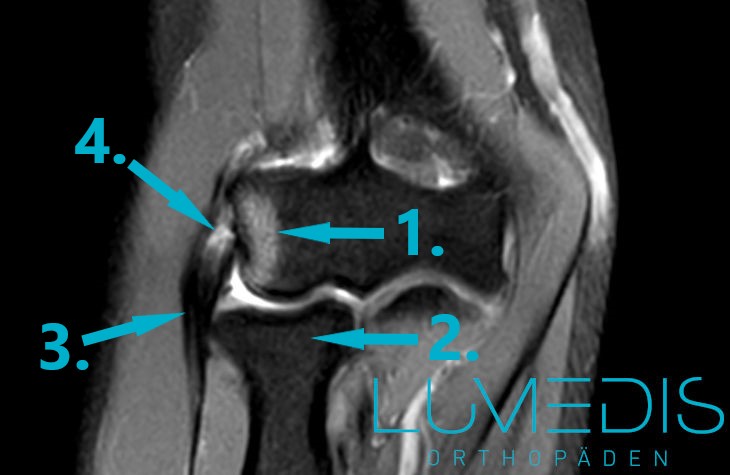

MRT eines schweren Tennisarms mit Sehnenanriss

MRT eines Ellenbogens

Türkiser Kreis = Riss der gemeinsamen Extensorensehne mit Entzündung